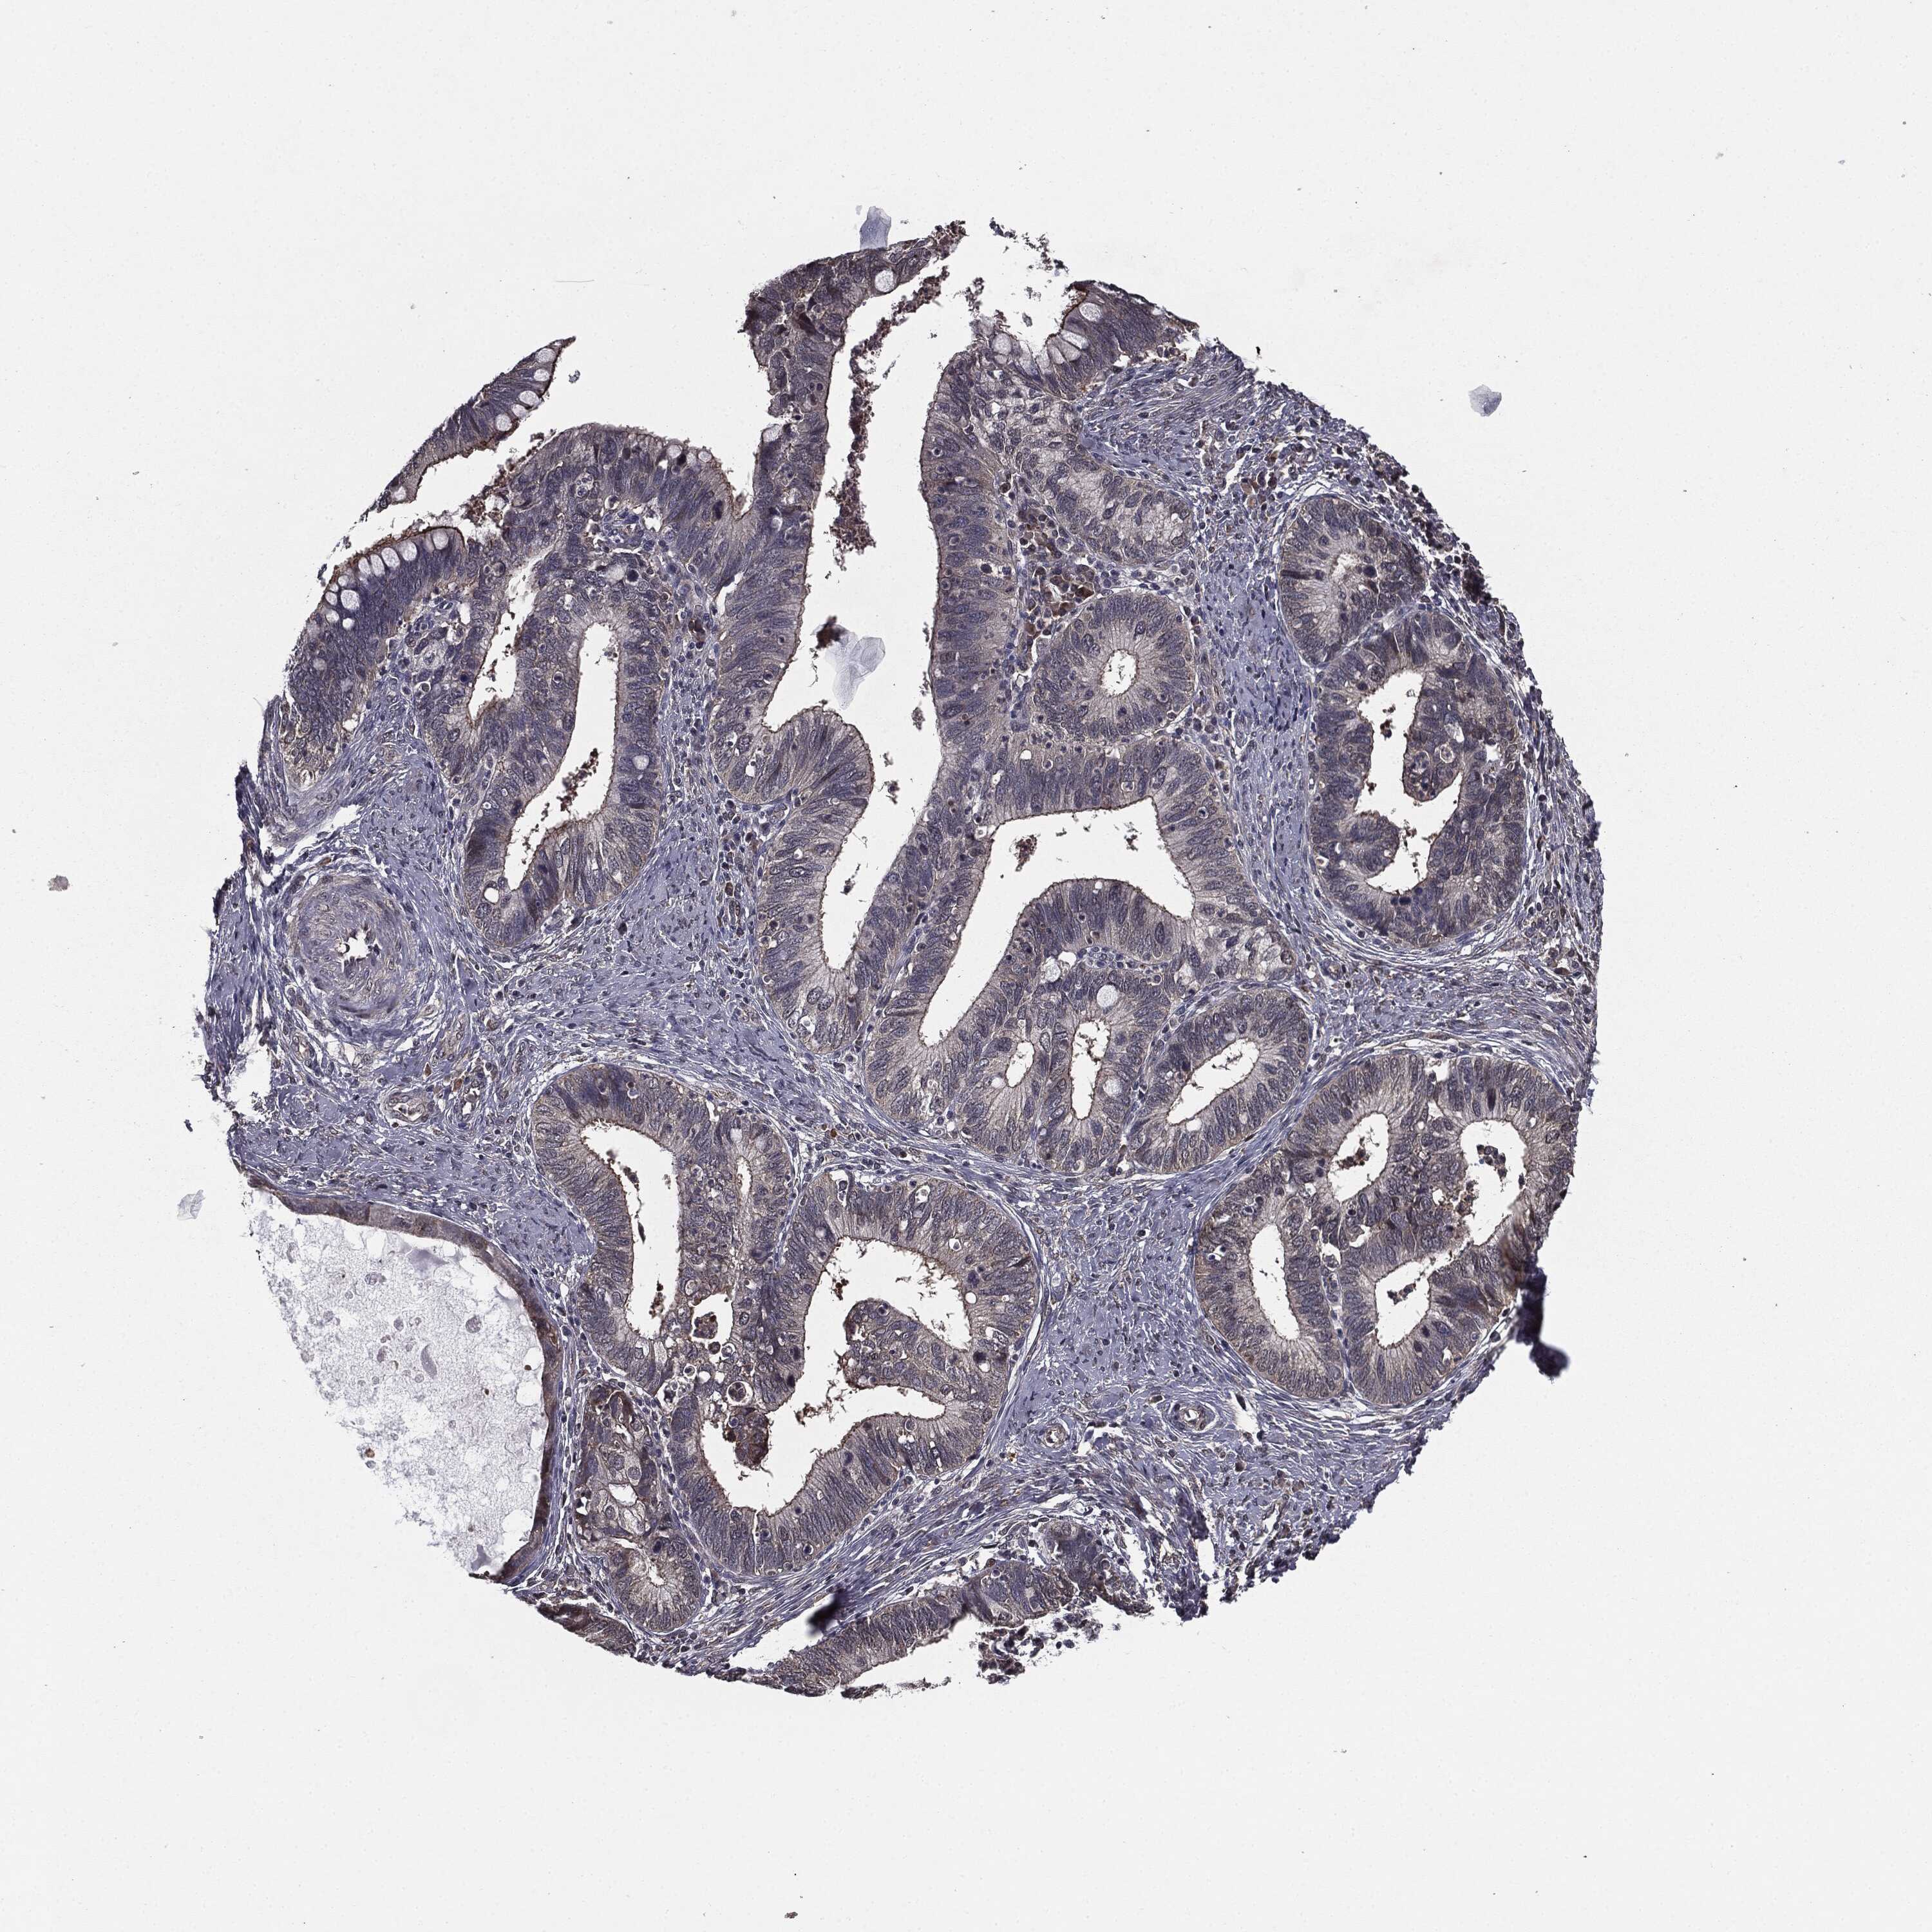

CERVICAL CANCER - Protein expressioni

A mouse-over function shows sample information and annotation data. Click on an image to view it in a full screen mode. Samples can be filtered based on level of antibody staining by selecting one or several of the following categories: high, medium, low and not detected. The assay and annotation is described here.

Note that samples used for immunohistochemistry by the Human Protein Atlas do not correspond to samples in the TCGA dataset.

Antibody stainingi

Antibody staining in the annotated cell types in the current human tissue is reported as not detected, low, medium, or high, based on conventional immunohistochemistry profiling in selected tissues. This score is based on the combination of the staining intensity and fraction of stained cells.

Each image is clickable and will lead to virtual microscopy that enables deeper exploration of all samples and also displays staining intensity scores, fraction scores and subcellular localization as well as patient and tissue information for each sample.

Antibody HPA052606

Antibody HPA077139

Staining

High

Medium

Low

Not detected

Intensity

Strong

Moderate

Weak

Negative

Quantity

>75%

75%-25%

<25%

None

Location

Nuclear

Cytoplasmic/membranous

Cytoplasmic/membranous,nuclear

Squamous cell carcinoma, NOS

Adenocarcinoma, NOS